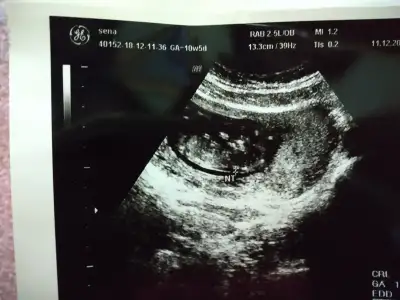

Amin canimm. Hislerim doğruymuş galiba erkekmis. Aşırı hareketli dedi. Ben hissediyorum hocam dedim. Hissedebilirsin tabi hiç durmuyor maşallah dedi.12. haftamdayim canım. Bu arada kulak burun boğaza da gittim. Antibiyotik öksürük şurubu gargara falan da yazdi. Lazım olursa isimlerini veririm. Sen ne hissediyorsun erkek mi kiz mi :)

Eklentiler

• IMG_20181211_192158.webp

IMG_20181211_192158.webp

60,2 KB · Görüntüleme: 96